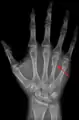

Fourth metacarpal bone

The fourth metacarpal bone (metacarpal bone of the ring finger) is shorter and smaller than the third.

A fractured right hand fourth metacarpal (boxer's fracture).